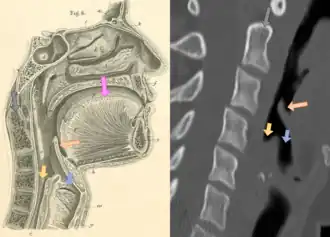

Neck X-ray showing thumbprint sign | |

Epiglottitis was historically mostly caused by infection by H. influenzae type b (commonly referred to as "Hib").[1] Following the introduction of the Hib vaccine, pediatric cases of epiglottitis fell from 3.47 cases per 100,000 children in 1980 to 0.63 cases in 1990[8] such that it is now more often caused by other bacteria, most commonly Streptococcus pneumoniae, Streptococcus pyogenes, or Staphylococcus aureus.[1] Predisposing factors include burns and trauma to the area.[1] The most accurate way to make the diagnosis is to look directly at the epiglottis.[3] X-rays of the neck from the side may show a "thumbprint sign" but the lack of this sign does not mean the condition is absent.[1]

On lateral C-spine X-ray, the thumbprint sign describes a swollen, enlarged epiglottis.[11] A normal X-ray, however, does not exclude the diagnosis.[11] An ultrasound may be helpful if specific changes are present, but its use (as of 2018) is in the early stages of study.[11]